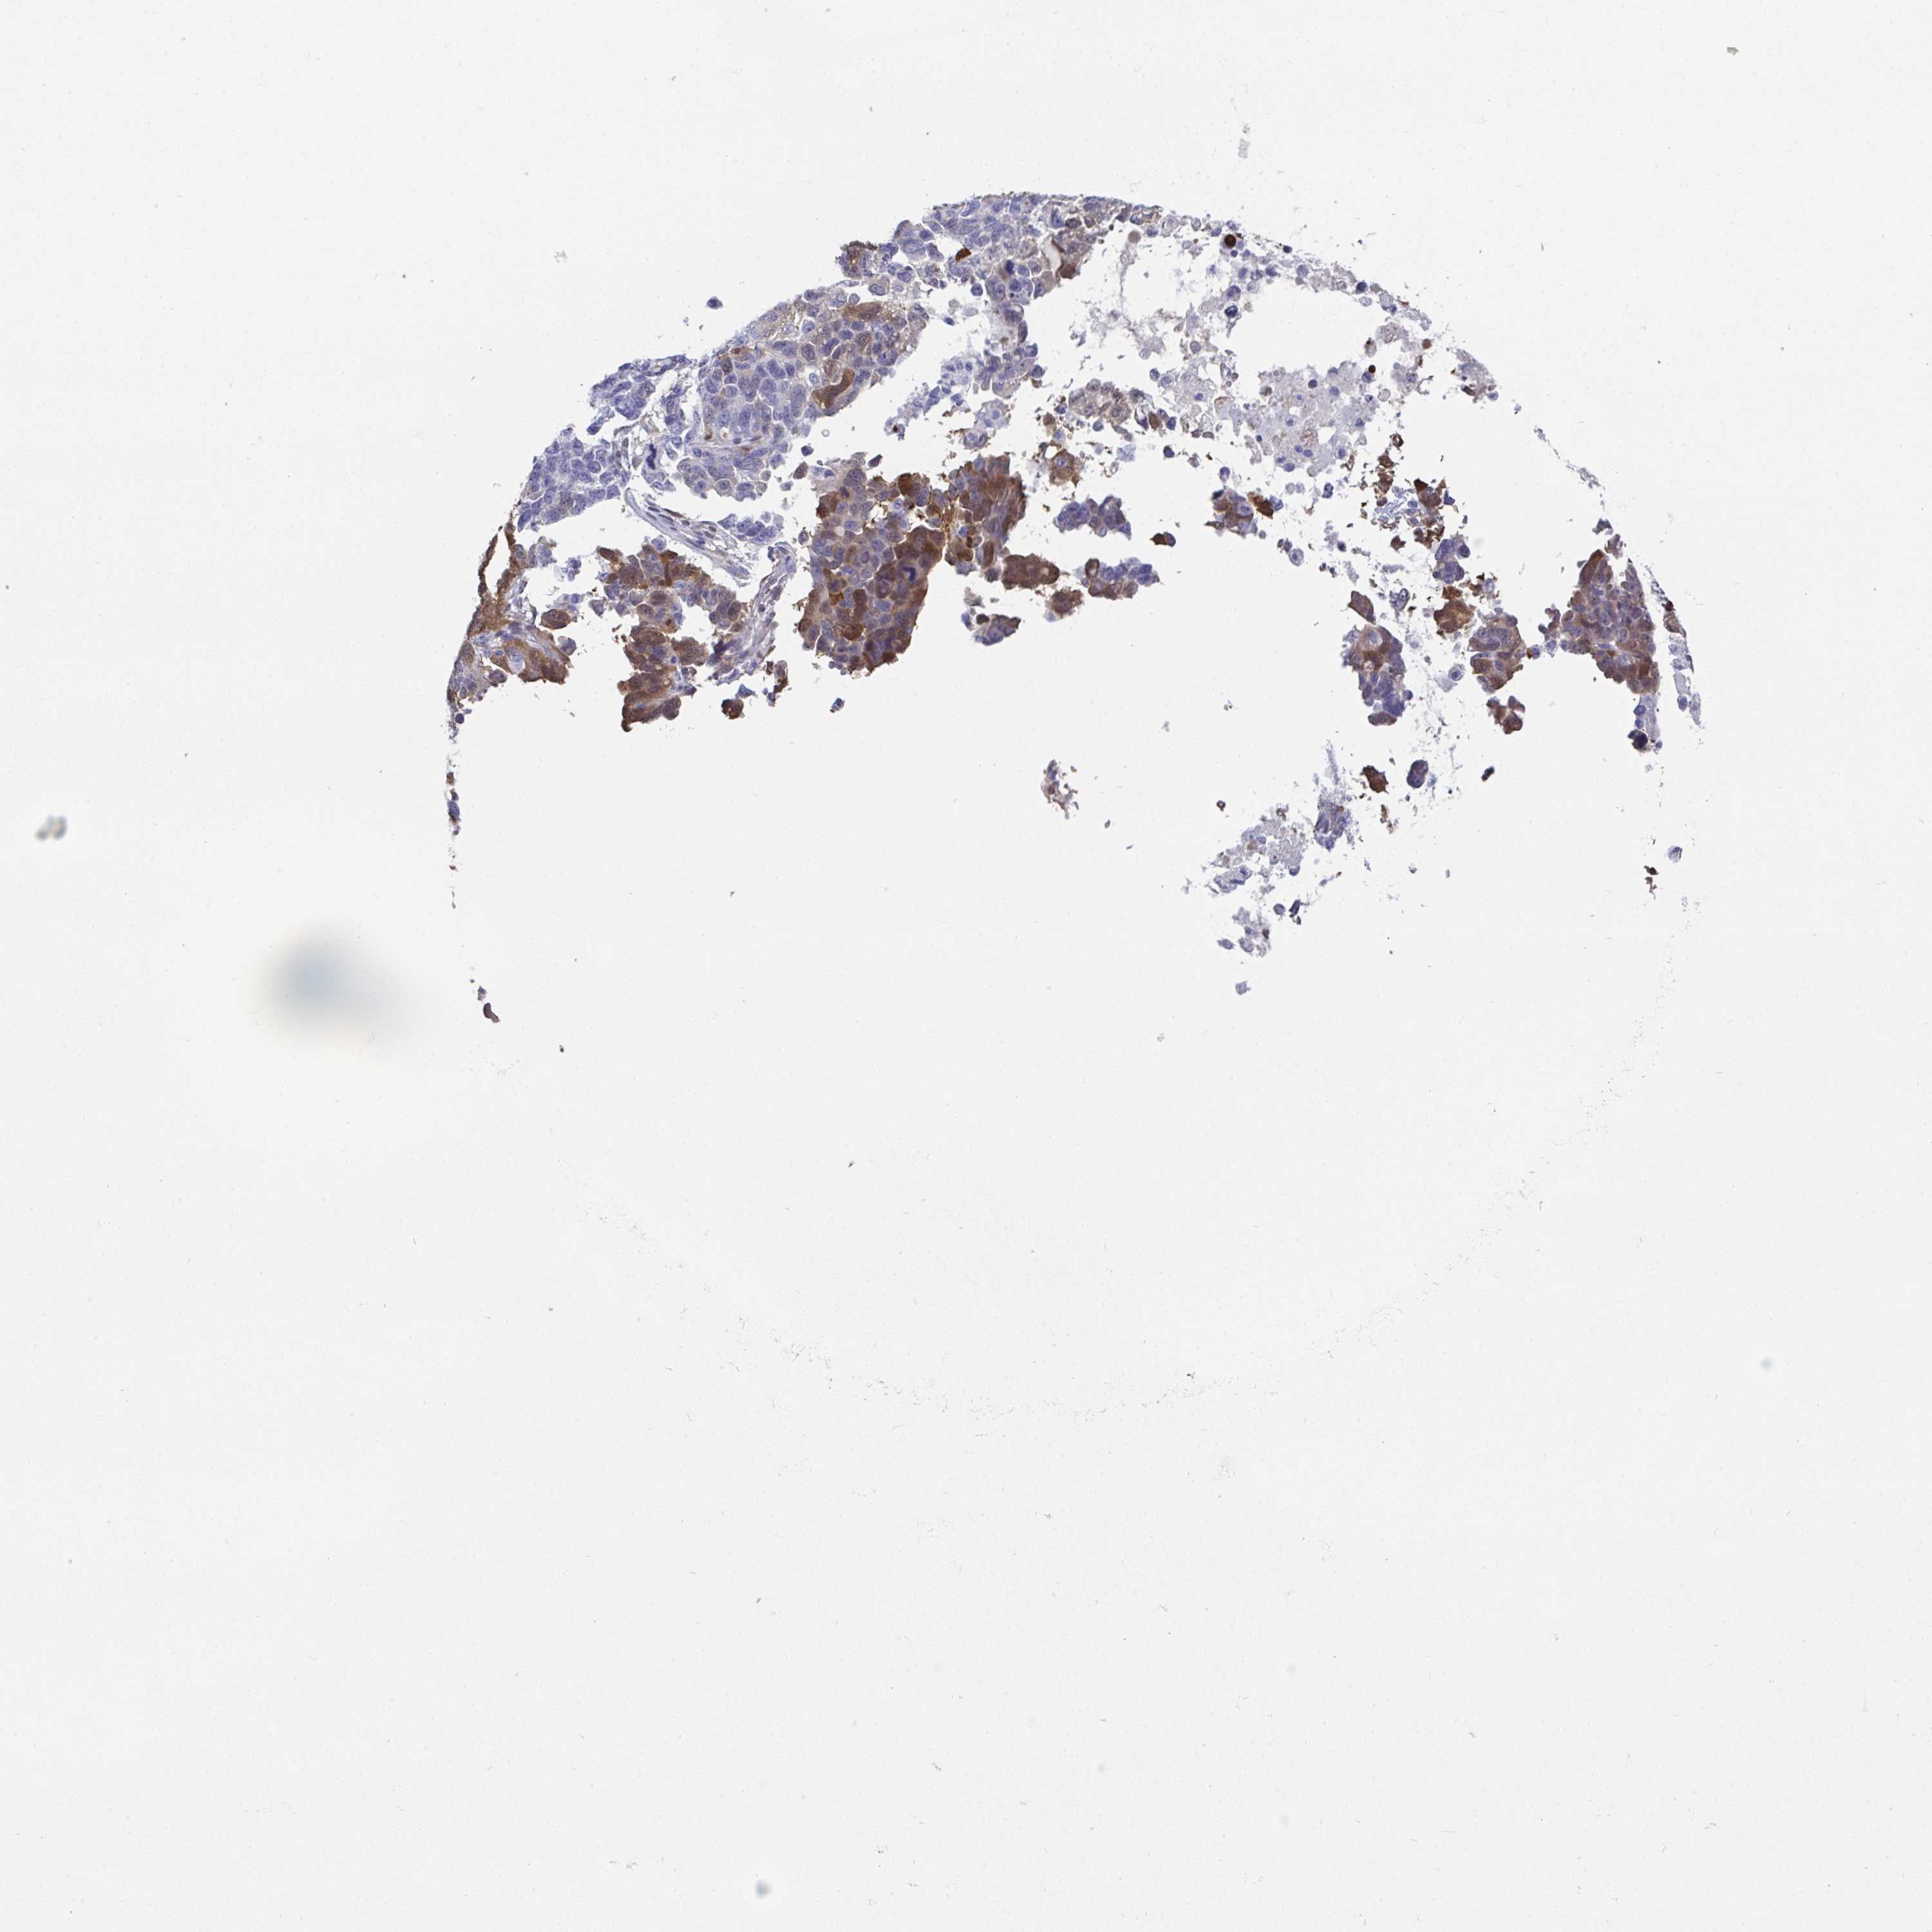

OVARIAN CANCER - Protein expressioni

A mouse-over function shows sample information and annotation data. Click on an image to view it in a full screen mode. Samples can be filtered based on level of antibody staining by selecting one or several of the following categories: high, medium, low and not detected. The assay and annotation is described here.

Note that samples used for immunohistochemistry by the Human Protein Atlas do not correspond to samples in the TCGA dataset.

Antibody stainingi

Antibody staining in the annotated cell types in the current human tissue is reported as not detected, low, medium, or high, based on conventional immunohistochemistry profiling in selected tissues. This score is based on the combination of the staining intensity and fraction of stained cells.

Each image is clickable and will lead to virtual microscopy that enables deeper exploration of all samples and also displays staining intensity scores, fraction scores and subcellular localization as well as patient and tissue information for each sample.

Antibody HPA007338

Antibody CAB018603

Antibody CAB019276

Staining

High

Medium

Low

Not detected

Cystadenocarcinoma, serous, NOS

Cystadenocarcinoma, mucinous, NOS

Carcinoma, endometroid

Carcinoma, NOS